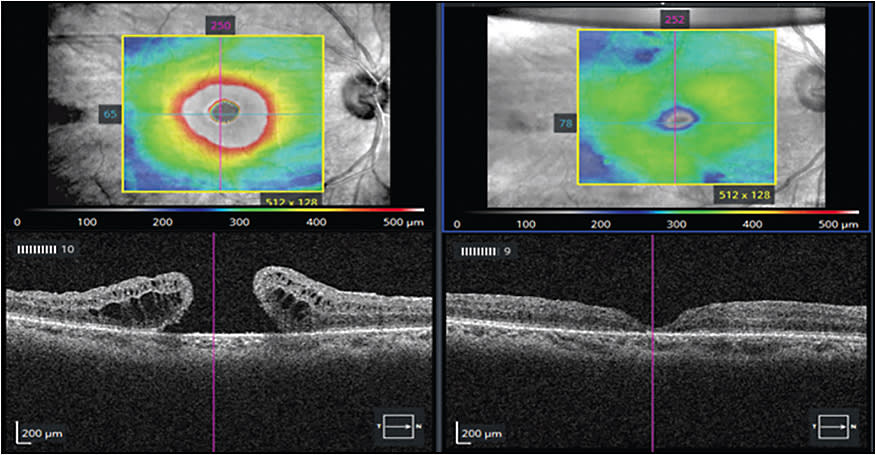

Mechanical manipulation of the retina with the goal of increasing tissue flexibility also facilitates the successful closure of MHs. Oliver and Wojcik first described this procedure in 2011.34 The technique relies on the creation of a controlled, localized macular detachment surrounding the MH using small-gauge cannulas (38-gauge or 41-gauge) connected to either a viscous fluid injection kit or syringe to administer balanced salt solution blebs contiguous with the MH (Figures 2 and 3). The edges of the MH can be brushed with a Tano diamond dusted scraper (Synergetics), a Flex Loop (Alcon), or a passive extrusion to further encourage closure. In some instances, to avoid creating additional defects in the retina, fluid can be refluxed through the macular hole into the subretinal space.35 The manipulation of the tissue is thought to release adhesions between the photoreceptors and retinal pigment epithelium, and may be particularly useful in situations with scarring which limits tissue mobility.34,36-38 Other methodologies rely on full-thickness retinal incisions. Charles et al first described an arcuate retinotomy technique, which requires full-thickness arcuate cuts temporal to the macular hole. Eighty-three percent of patients had successful closure of their MH and 50% had visual improvement.39 Other iterations of this protocol involve 5 perifoveal radial incisions, ending at the edge of the hole, or double arcuate relaxing retinotomies near the inferiortemporal and superotemporal arcades.40,41